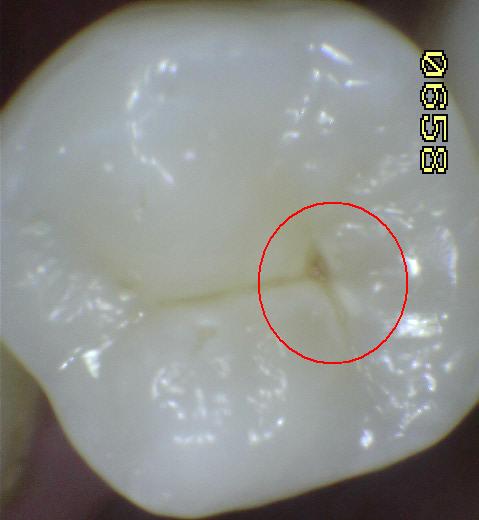

Código 3